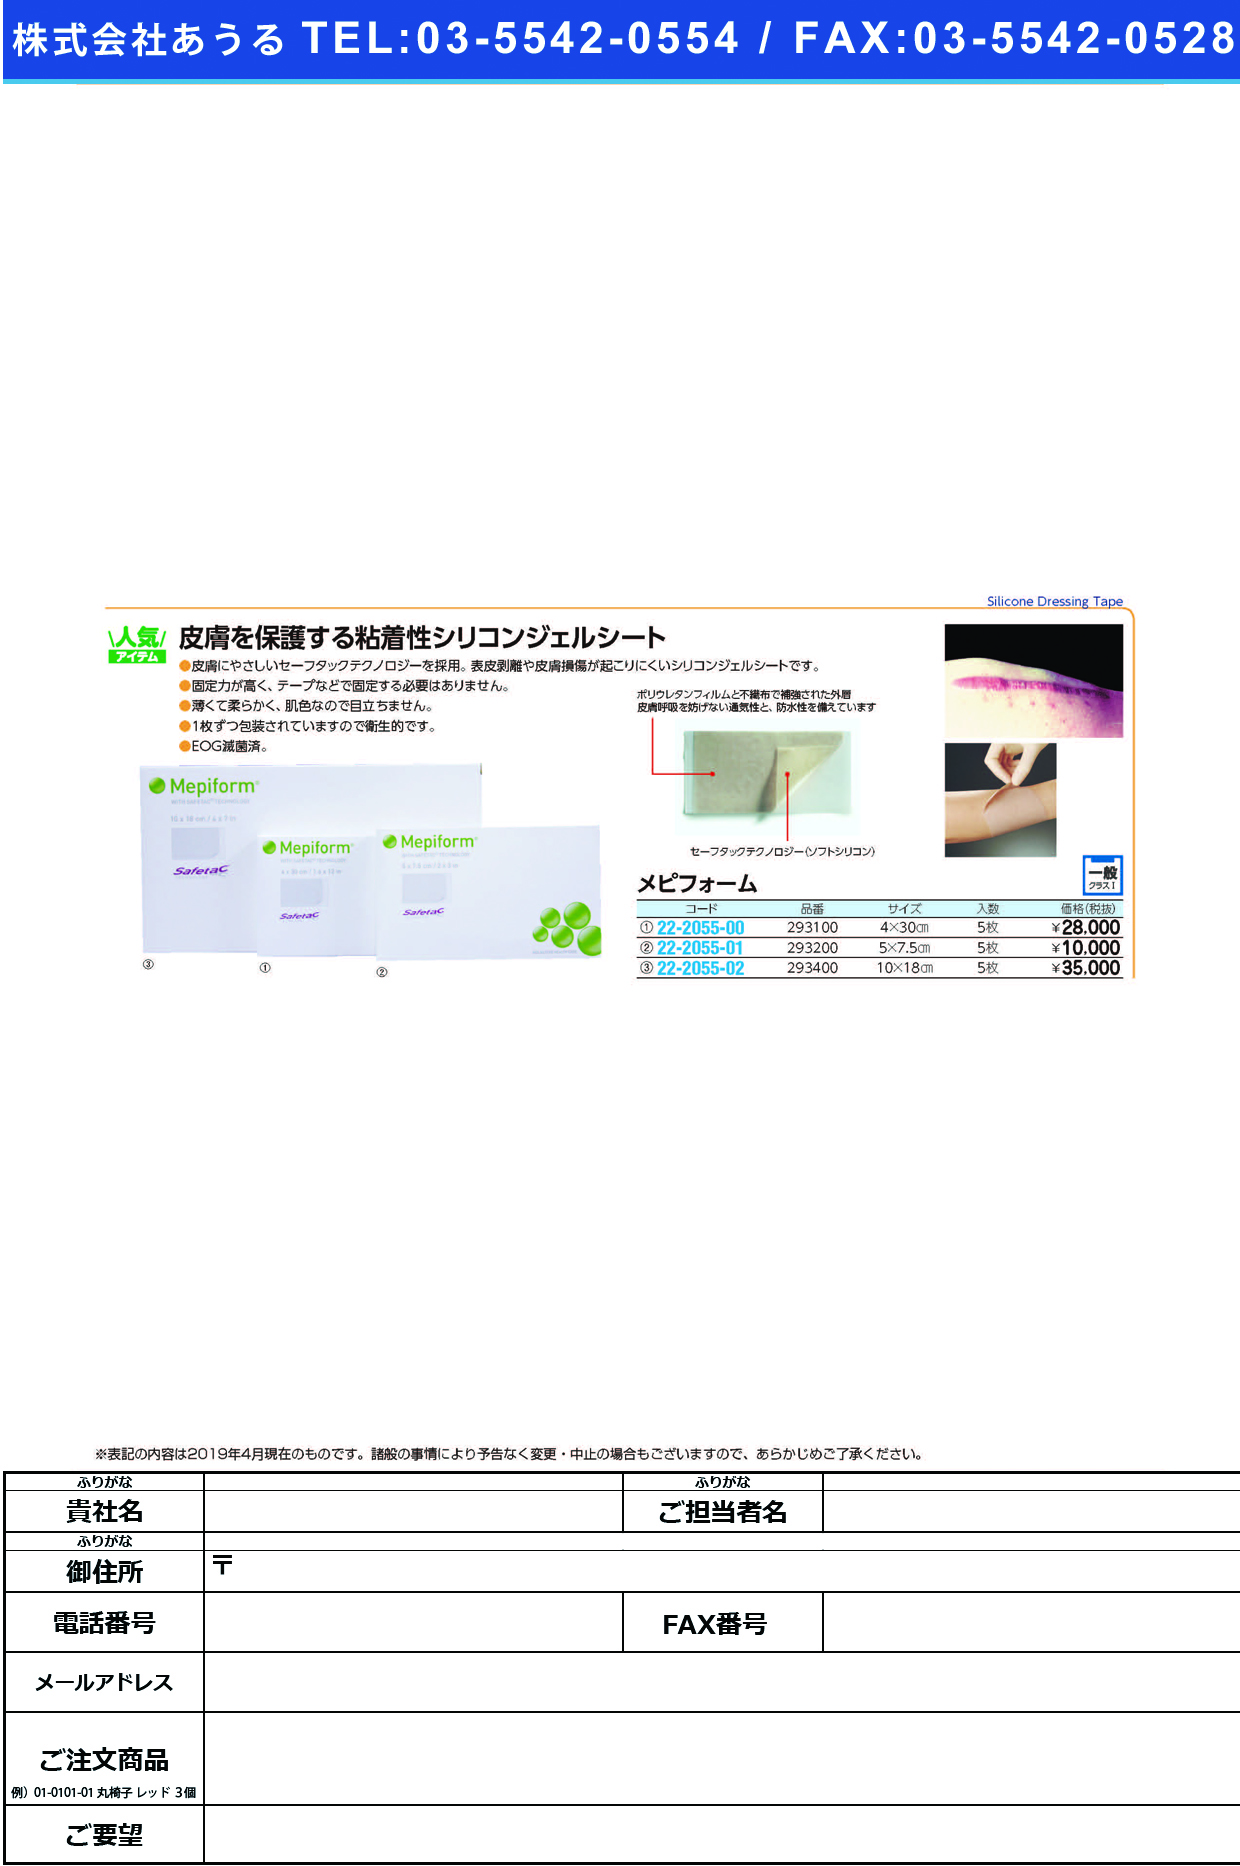

皮膚を保護する粘着性シリコンジェルシート

●皮膚にやさしいセーフタックテクノロジーを採用。表皮剥離や皮膚損傷が起こりにくいシリコンジェルシートです。●固定力が高く、テープなどで固定する必要はありません。●薄くて柔らかく、肌色なので目立ちません。●1枚ずつ包装されていますので衛生的です。●EOG滅菌済。

| 商品名 | (22-2055-00)メピフォーム 293100(4X30)5マイイリ メピフォーム(メンリッケヘルスケア)【1箱単位】【2019年カタログ商品】 |

| 商品コード | 22-2055-00 |

| 標準価格 | 28,000円(税抜き) |

| 会員価格 | 19,765円*(税抜き) |

| メーカー | メンリッケヘルスケア |

FAXでもご注文も承っております。こちらのオーダーシートをプリントアウトして、必要事項をご記入の上、FAXしてください。※クリックするとPDFファイルに切り替わります。